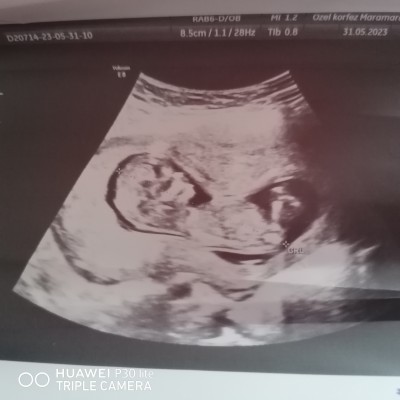

Kızlar doktor 12 +3 de erkeğe benziyor dedi ama net değil sizce netleşmezmi bu tarihte özele gittim bu arada image

Gebelik haftası 13 1